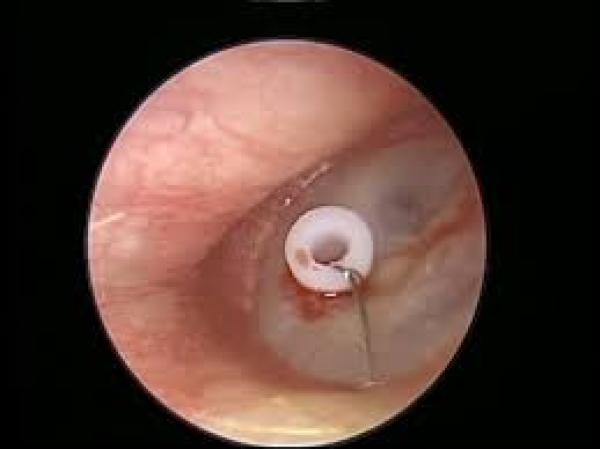

YENİ!!! EFFÜZYONLU OTİTİS MEDİALI HASTALARDA VENTİLASYON

ORTA KULAKTA SIVI BİRİKİMİNDE (EFFÜZYONLU OTİTİS MEDİA) Orta kulakta sıvı oluşumu alerjik nedenlerle, genizeti varsa, çevresel faktörler (özellikle h...